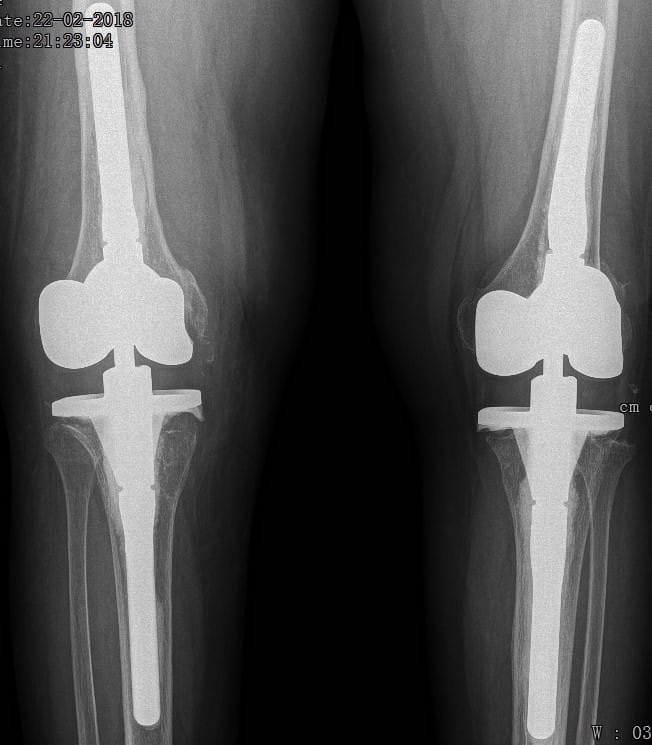

Although there has been an attempt to perform knee replacement in the 19th and early 20th century, Total Knee replacement surgery has come a long way since 1970s with continuous improvement in the design of implants and fixation techniques. Success from Charlney’s hip replacement surgery got surgeons and engineers interested again leading to modern-day implants. It has been successfully being performed worldwide from 1980 onwards. Diseased part of femur and tibia are removed using special instruments and metal implants mimicking design of femur and tibia are inserted using antibiotic-laden polymethyl methacrylate (bone cement). A polyethylene inset is fixed onto the tibial implant thus allowing movement at the knee joint. The undersurface of patella may be replaced with a patellar button in some cases. Due to improved technique and implant design, this surgery has gained immense popularity and has given a new lease of life for the patients suffering with arthritis of the knee joint. Patients can walk comfortably with the help of support following surgery and aren’t dependent on others for day-to-day life activities. Quality of postoperative care in recent times has further boosted the confidence among the patients undergoing this surgery. Patients are taught to strengthen the thigh muscle post-operatively and encouraged to become mobile. Gradually, they learn to climb stairs and later they walk around independently without any aided support. It is recommended that patients should not sit on the floor or squat. This helps maintain the longevity of the implants. As per the American Association of Orthopaedics, success rate of total knee replacement after 15 years is almost 90% and at the end of 25 years is almost 82%.

In total knee replacement surgery, we remove the damaged area over the femur, tibia and patella in the knee joint. It is replaced it with metal implants which are in the shape of these bones. These metal implants are fixed over your bone with the help of bone cement. Implants come in various sizes and you will get the best fit suited for you.